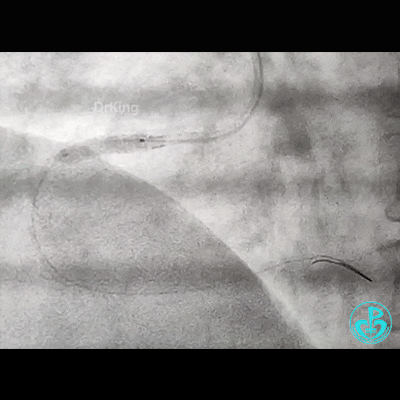

此时,鞘管外GC已经扭曲,更换JR 4.0,看右冠开口。

导丝怎么扩右冠近段弥漫性病变中远段闭塞顺利开通并植入支架,哪知道故事才刚刚开始!!!_https://www.jmylbn.com_新闻资讯_第22张

导丝怎么扩右冠近段弥漫性病变中远段闭塞顺利开通并植入支架,哪知道故事才刚刚开始!!!_https://www.jmylbn.com_新闻资讯_第23张

反复操作GC,疑似右冠开口已经夹层,此时心电图无异常!

补3.5×12mm支架一枚。

导丝怎么扩右冠近段弥漫性病变中远段闭塞顺利开通并植入支架,哪知道故事才刚刚开始!!!_https://www.jmylbn.com_新闻资讯_第24张

导丝怎么扩右冠近段弥漫性病变中远段闭塞顺利开通并植入支架,哪知道故事才刚刚开始!!!_https://www.jmylbn.com_新闻资讯_第25张

导丝怎么扩右冠近段弥漫性病变中远段闭塞顺利开通并植入支架,哪知道故事才刚刚开始!!!_https://www.jmylbn.com_新闻资讯_第26张

导丝怎么扩右冠近段弥漫性病变中远段闭塞顺利开通并植入支架,哪知道故事才刚刚开始!!!_https://www.jmylbn.com_新闻资讯_第27张

这台20分钟就能完成的手术,耗时达2个小时!